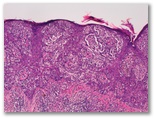

¿Nevus de Reed?

Diagnostico